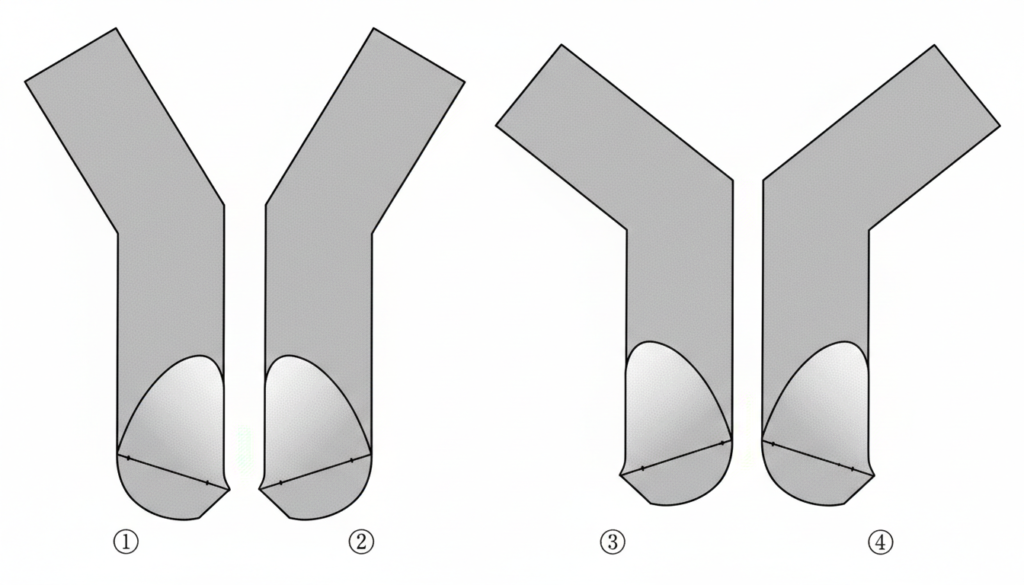

午前-71

グレーシータイプキュレットを刃部先端からみた模式図を示す。下顎右側第一大臼歯舌側遠心の縁下歯石を除去するのに適しているのはどれか。 1つ選べ。

a. ①

b. ②

c. ③

d. ④

解答を見る

d